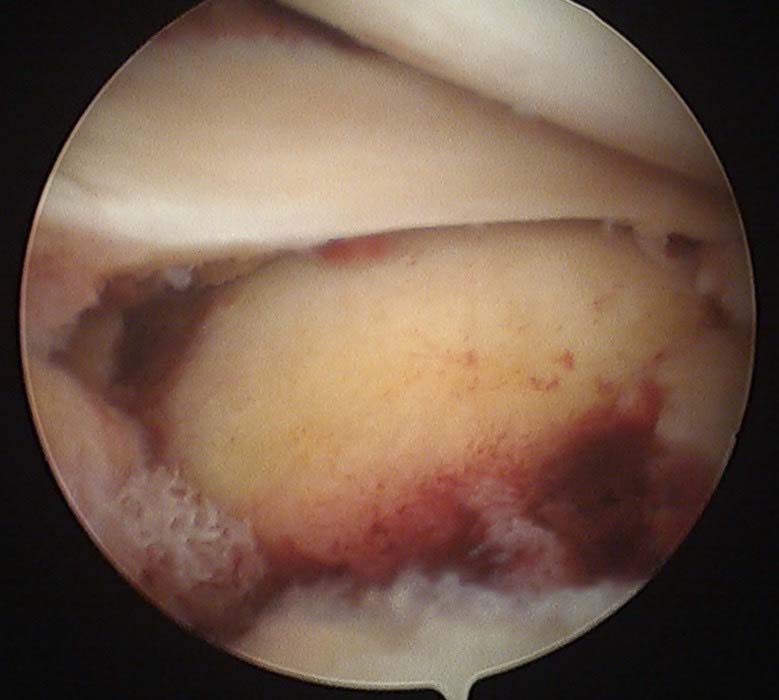

高市58歲張姓女長照服務員上班途中不幸遭汽車擦撞左膝挫傷,後送大同醫院急救,經X 光與電腦斷層掃描確診左膝脛骨骨折,骨科醫師黃柏樺建議施作關節鏡輔助骨折復位與鋼板鋼釘內固定手術,術後3個月可正常行走,成為長庚醫療接手營運後首名完成關節鏡手術病友。

關節鏡術僅2至3個約0.5公分傷口,相較傳統開刀,兼具疼痛少、恢復期短、降低後遺症風險等特性,黃柏樺說,手術仰賴經驗及技巧,未來續推廣嘉惠更多病友,但因手術屬自費,建議尋求專科醫師評估,決定適切治療方式。圖/長庚醫院提供、文/高培德